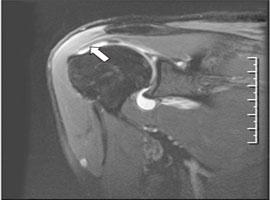

- 회전근개 파열

- 어깨뼈 사이에 위치한 4개의 근육(회전근개) 중 하나 이상이 끊어지거나 손상된 상태입니다.

- 정의: 어깨 내 회전근개(4개의 근육 힘줄) 중 하나 이상이 끊어지거나 손상된 상태입니다.

- 증상: 팔을 위로 올릴 때 통증이 심하고, 마찰음이 들릴 수 있습니다.

- 팔을 들어 올린 채 10초 이상 유지하기 힘들며, 밤에 통증이 악화하는 경향이 있습니다.

- 스스로 팔을 올리지 못해도, 다른 사람이 들어주면 팔이 올라갑니다.